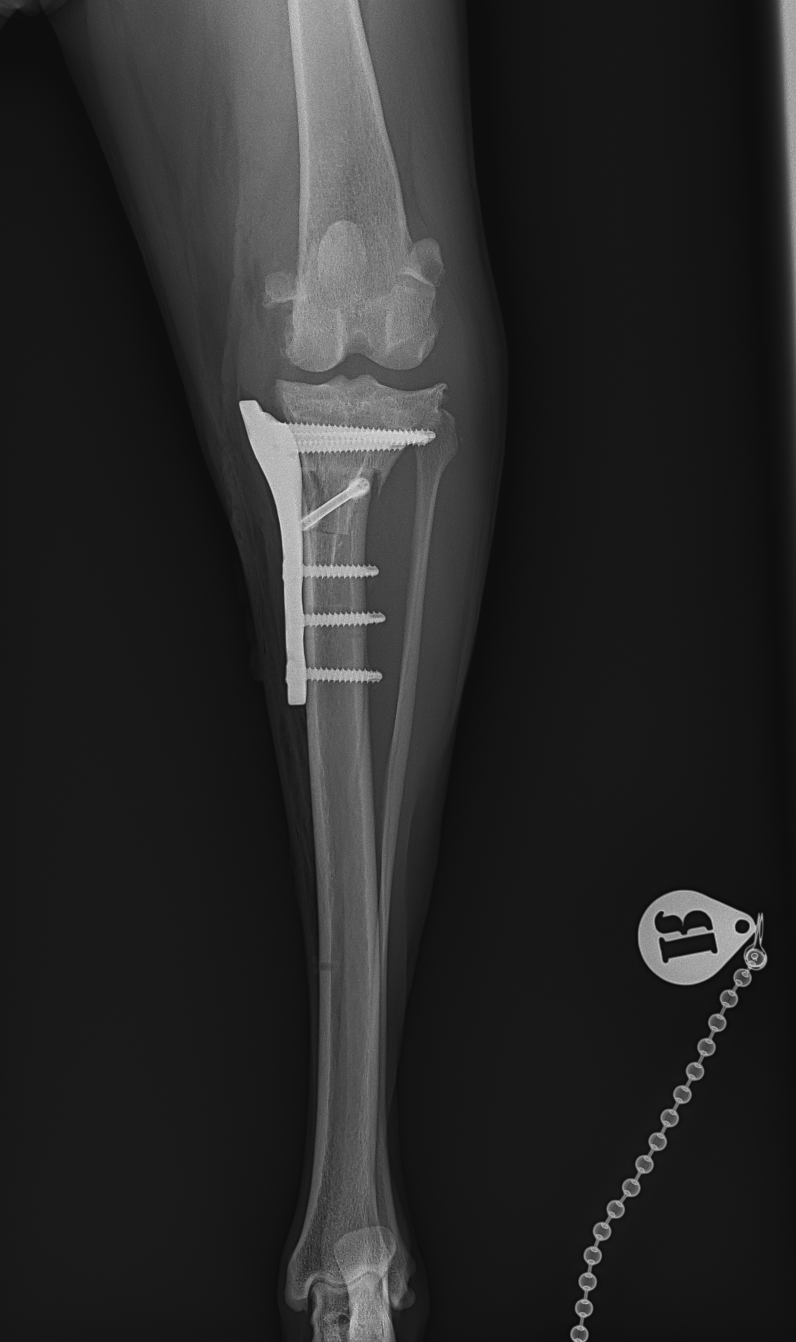

大型犬の前十字靭帯疾患(慢性経過)に対するCBLO #254 大型犬のCrCLDの患者さんに3.5 Rita Locking CBLOで対応しました。今後はリハビリテーションが非常に重要になります。生涯にわたって膝関節のケアを行なっていく必要があります。 症例カテゴリー 放射線治療整形外科軟部組織外科脳神経外科内科腫瘍外科救急・集中治療リハビリテーション科腫瘍内科内視鏡科脳神経科呼吸器外科中医・漢方猫の腎移植循環器科